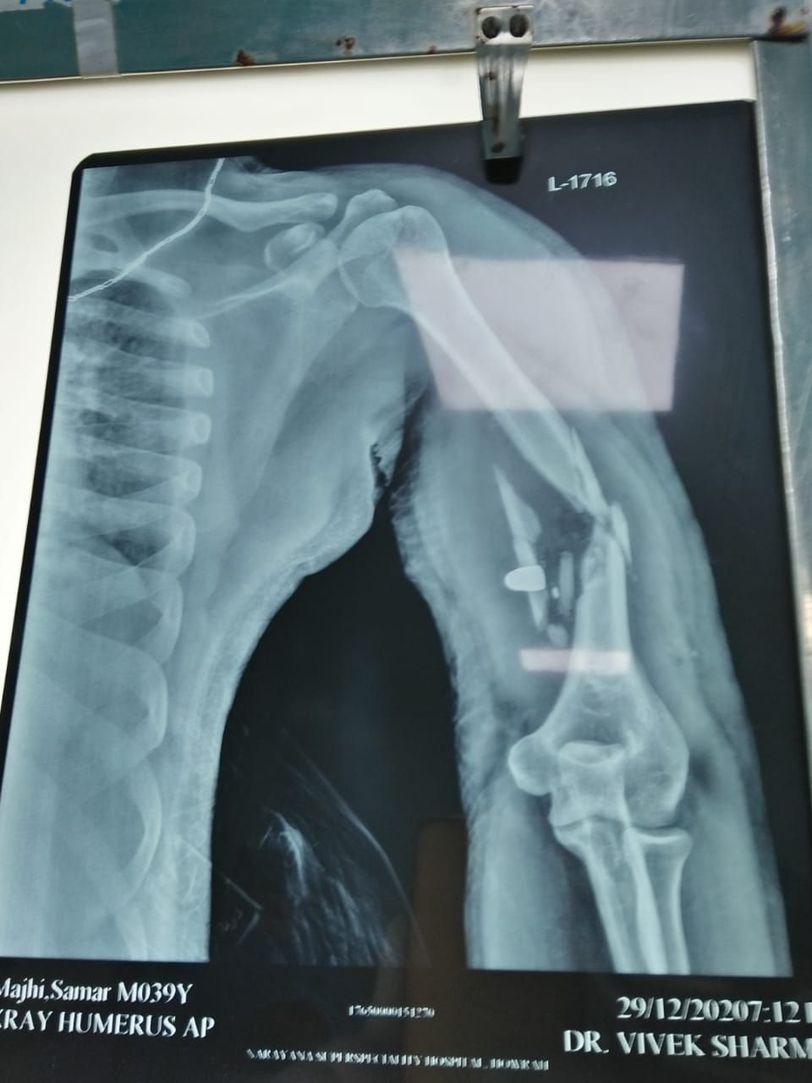

What is your treatment!

ORIF

ORIF stat!